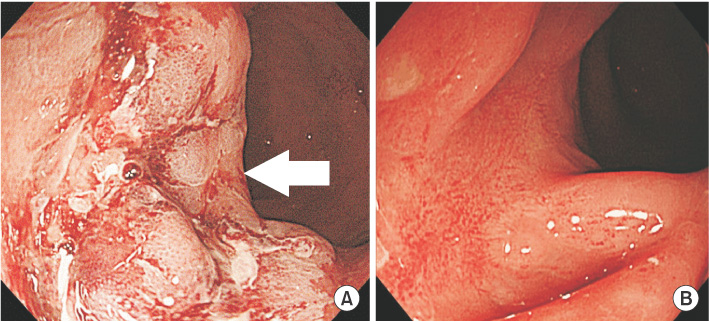

Colonoscopy showed a hemorrhagic and circumferential ulcerated mass with edema in the anterior rectal wall located 5 cm from the anal verge (

Fig. 1A). Abdominopelvic CT exhibited an area of rectal wall thickening with perirectal fatty infiltration and enlargement of multiple small mesocolic lymph nodes, consistent with rectal cancer (

Fig. 4). Two months after conservative management with stool softener and pain control, clinical symptoms of patient improved. Follow-up colonoscopy showed that the lesion markedly improved with remnant ulcerative scarring (

Fig. 1B).

Fig. 1Endoscopic findings. (A) Colonoscopy shows a broad-based rectal lesion with irregular surface and hemorrhagic ulceration (arrow) (B) Rectal lesion is markedly improved with remnant ulcerative scarring two months later.